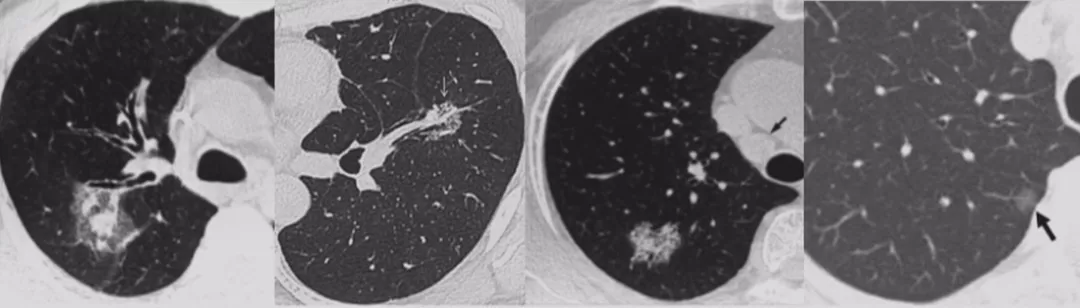

如上图所示,一般来说这么小的病灶我们可能忽略,但这个病人做了手术,不仅是恶性肿瘤,而且是微浸润腺癌。实际上我们在临床上要把这么多结节甄别出来,是十分具有挑战性的。病人一旦患有肺结节,也面临着很多问题,比如焦虑、心理压力等。所以我们既不能过度诊断,但也不能延误诊断。

在临床上经常手术切除后发现是AAH,关于AAH的病人是否需要手术还存在很大的争议,有的认为不需要手术,观察就可以。那么我们在术前怎么评判是否为AAH?其实具有一定特征。一般来说,多位于肺外周,多<5mm,圆形或类圆形,边界清楚,多发更常见,绝大部分是均匀的纯磨玻璃影,里边没有实性成分。组织学检查AAH呈轻度到中度非典型立方柱状上皮细胞沿肺泡和呼吸性细支气管上皮增殖,无浸润,这样在临床上诊断AAH应该没有问题。但是,如下图所示,这个病人是多灶性病变,现在多灶性结节有所增多,会给临床的处理上带来一定压力。

小细胞肺癌以中央型多见,但是也有少数为周围型病灶。多为单个实性结节或肿块,可见分叶、毛刺、血管集束征、胸膜牵拉征。实际上我们很难从影像学上判断出小细胞肺癌的病理类型,往往是活检或者手术以后才能证实。如下图示,这属于I期的小细胞肺癌,进行手术的效果非常好。所以对于周围型小细胞肺癌,如果在结节很小的时候判断出来就做了手术,疗效非常好。我们知道小细胞肺癌是肺癌中治疗效果最差的,恶性程度是最高的。如果早期手术,仍然能够起到很好的效果。